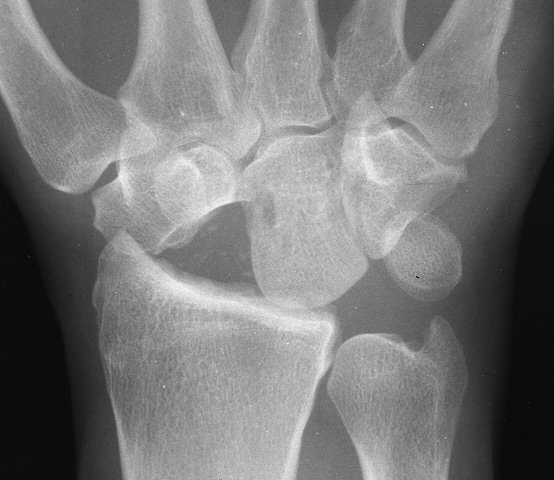

Proximal Row Carpectomy

Proximal row carpectomy for painful scapholunate dissociation with radioscaphoid arthritis. These are steps taken from the video at the bottom of this page.